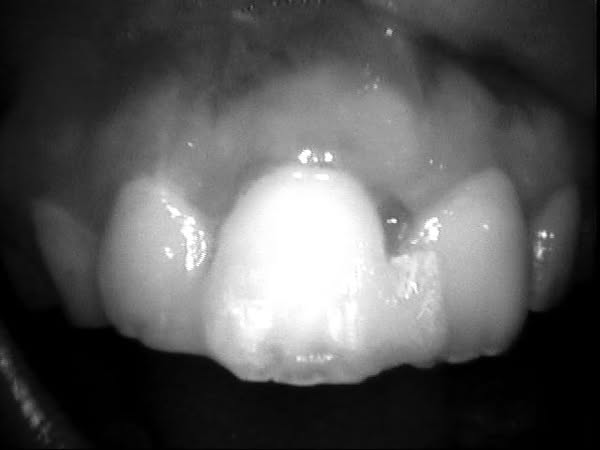

仔細幫她檢查受傷的牙齒,發覺撞擊力道還真的不輕,而且有多顆牙齒鬆動與脫落的現象。

仔細幫她的受傷牙齒,先用X光片確定沒有明顯的不可逆裂痕後,接著認真清創,再把受傷脫位牙齒復位後,將它跟旁邊健康牙齒整排緊緊的黏著在一起。暗自希望藉由這樣的保護,看能不能有機會讓原本斷裂的軟硬組織,有重新再癒合與固著機會。

(急診當下照片由於稍嫌怵目驚心,因此選擇急診後一週的傷口逐步修復照片)